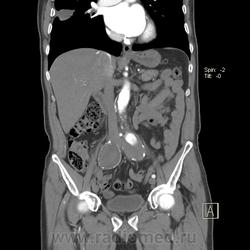

Пациент лежит в кардиологии. Прислали на аортографию. 2 врача УЗИ несколько разошлись в диагнозах: одна видит тромбированную аневризму брюшной аорты, другая - тромбоз нижней полой вены.

А мы получили вот такие красивые картинки.

Шикарно! Тромбированная аневризма инфраренального отдела (над бифуркацией), бифуркации и общих подвздошных артерий, синдром Лериша справа.

И еще маленькая аневризмочка наружной подвздошной слева. Честно говоря, меня больше всего впечатлили коллатерали, благодаря которым клинически он вообще не соответствует исследованию. Конечности теплые, пульсация слабая, но как-то прослеживается...